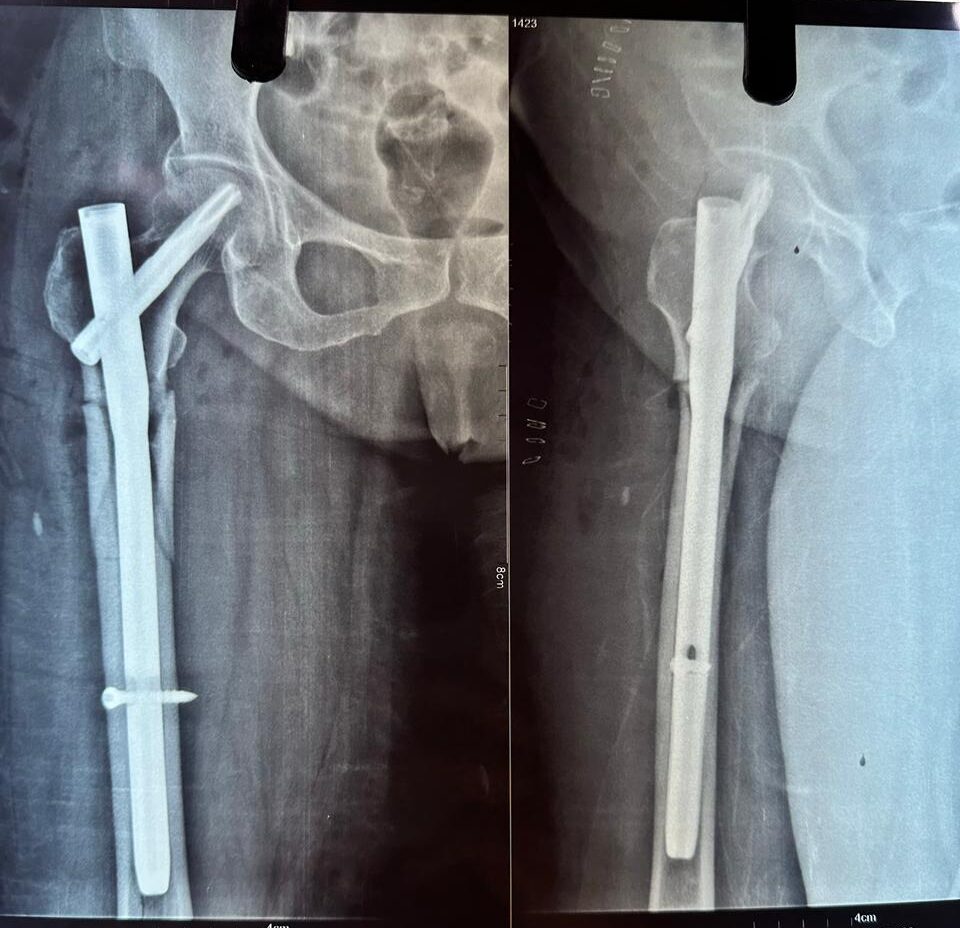

Moments That Mark Meaningful Recovery

Witness real patient transformations at The Ortho Clinic through images that reflect successful treatments and restored mobility.